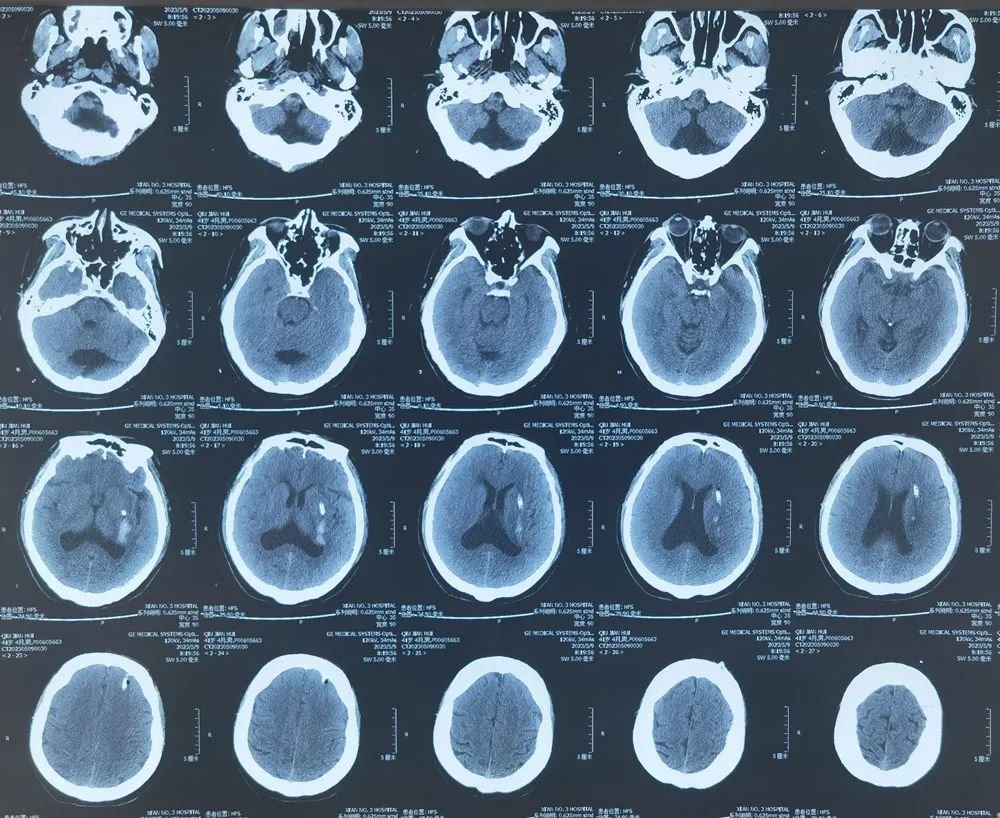

术后,影像检查显示,高先生的脑部血肿几乎完全消失,肢体功能也有明显改善。

▲手术后